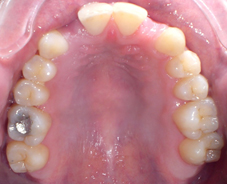

Photo 1 : Arcade maxillaire après traitement orthodontique, agénésie des incisives latérales maxillaires

Photo 2 : Bridge collé en cantilever, piliers de bridge 11-21